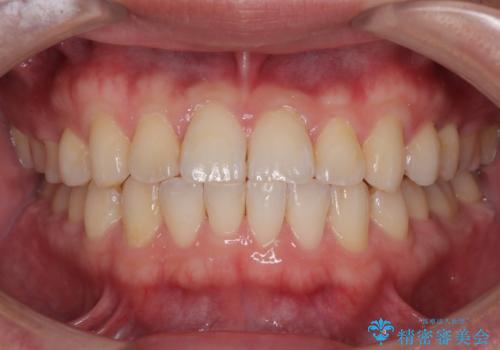

**前歯のデコボコ(叢生)**が整い、歯列全体が美しく改善

シザーズバイトの奥歯も正常なかみ合わせに改善

捻転歯も回転が修正され、全体的に清掃性・咀嚼効率が向上

患者様にも「大人になってから矯正を始めることに不安もありましたが、思っていたよりも短期間で治療が終わって本当にうれしいです。前歯のガタガタも気にならなくなり、笑うことに自信が持てるようになりました!」と喜んでいただけました。